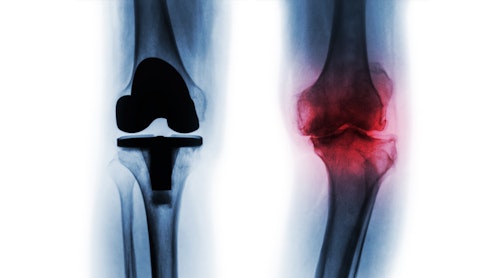

It is the knee surgery of choice for professional players and amateur athletes. This type of surgery is minimally invasive, which makes it very low risk, is typically done in less than an hour and has an extremely fast recovery rate. In some ways, this type of surgery has replaced more invasive and complicated surgeries such as total knee replacement.

A knee replacement -also known as knee arthroplasty- is a surgical the procedure where damaged bones and cartilage are replaced. In this treatment, the surgeon cuts the damaged bone and cartilage from the shin and kneecap and replaces it with an artificial joint or a prosthesis. Click below to learn more about Knee replacement surgery.